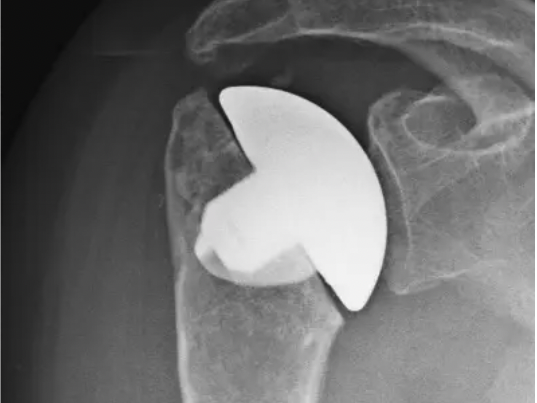

Omarthrose

Die Arthrose des grossen Schultergelenkes, sogenannt Omarthrose, macht sich glücklicherweise erst spät bemerkbar, da es sich im Vergleich zur Hüfte oder Knie kein tragendes Gelenk ist.

Das erste Zeichen einer Omarthrose sind häufig Bewegungseinschränkungen. Im Verlauf kommt dann der Schmerz.